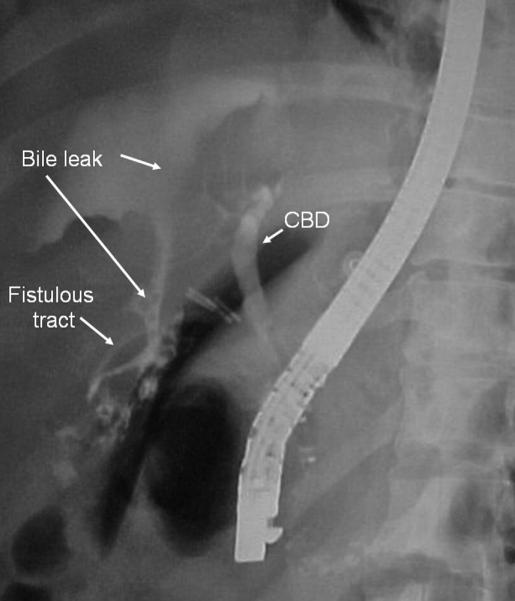

T-tube choledochotomy has been an established practice in common bile duct exploration for many years. Although bile leaks, biliary peritonitis, and long-term postoperative strictures have been reported and are directly associated with the placement or removal of the T-tube, the severity of these complications may often be underestimated by surgeons. We present the case of a 31-year-old male patient who developed biliary peritonitis and septic shock after removal of a T-tube and illustrate one of the catastrophic events that may follow such procedures. Literature shows that these complications may occur more frequently and have higher morbidity and mortality than other less invasive procedures. This article reviews the advances in laparoscopic and endoscopic techniques, which provide alternative therapeutic approaches to choledocholithiasis and allow the surgeon to avoid having to perform a choledochotomy with T-tube drainage.

胆总管切开T管引流术多年来一直是胆总管探查的常用术式。尽管已有胆汁漏、胆汁性腹膜炎及术后长期胆管狭窄的报道,且这些情况与T管的放置或拔除直接相关,但外科医生往往会低估这些并发症的严重程度。我们报告一例31岁男性患者,其在拔除T管后发生胆汁性腹膜炎和感染性休克,并阐述了此类手术可能引发的灾难性事件之一。文献表明,与其他侵入性较小的手术相比,这些并发症可能更频繁发生,且发病率和死亡率更高。本文综述了腹腔镜和内镜技术的进展,这些技术为胆总管结石提供了替代治疗方法,使外科医生无需进行胆总管切开T管引流术。